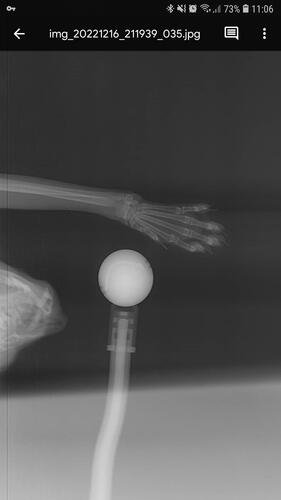

Depois de algumas consultas e até mesmo um diagnóstico errado, enfim descobriram que eu estava com as patinhas fraturadas, e pela forma como estavam a explicação era apenas uma: fui mais um alvo da maldade humana.

Eu preciso operar as patas o quanto antes, pois venho tendo perda óssea e mal consigo usar minha caixa de areia. Vivo apenas deitada e é minha mãe quem me alimenta e me da água na boca, além de levar na caixina, pois como podem ver nas fotos, minhas patas estão tortinhas e não consigo mais o mínimo de apoio.